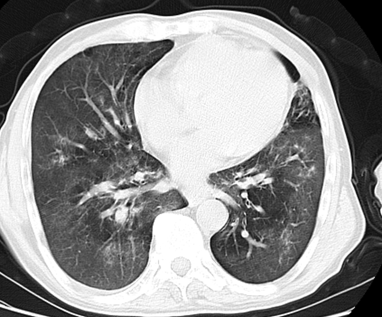

患者影像学表现

(上图为检查结果)